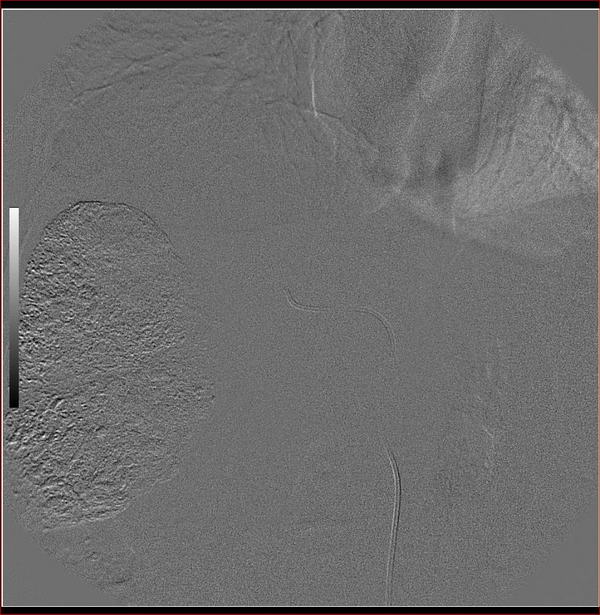

标题: DSA0138:F38Y,肝脏病变

第二次(50天后)